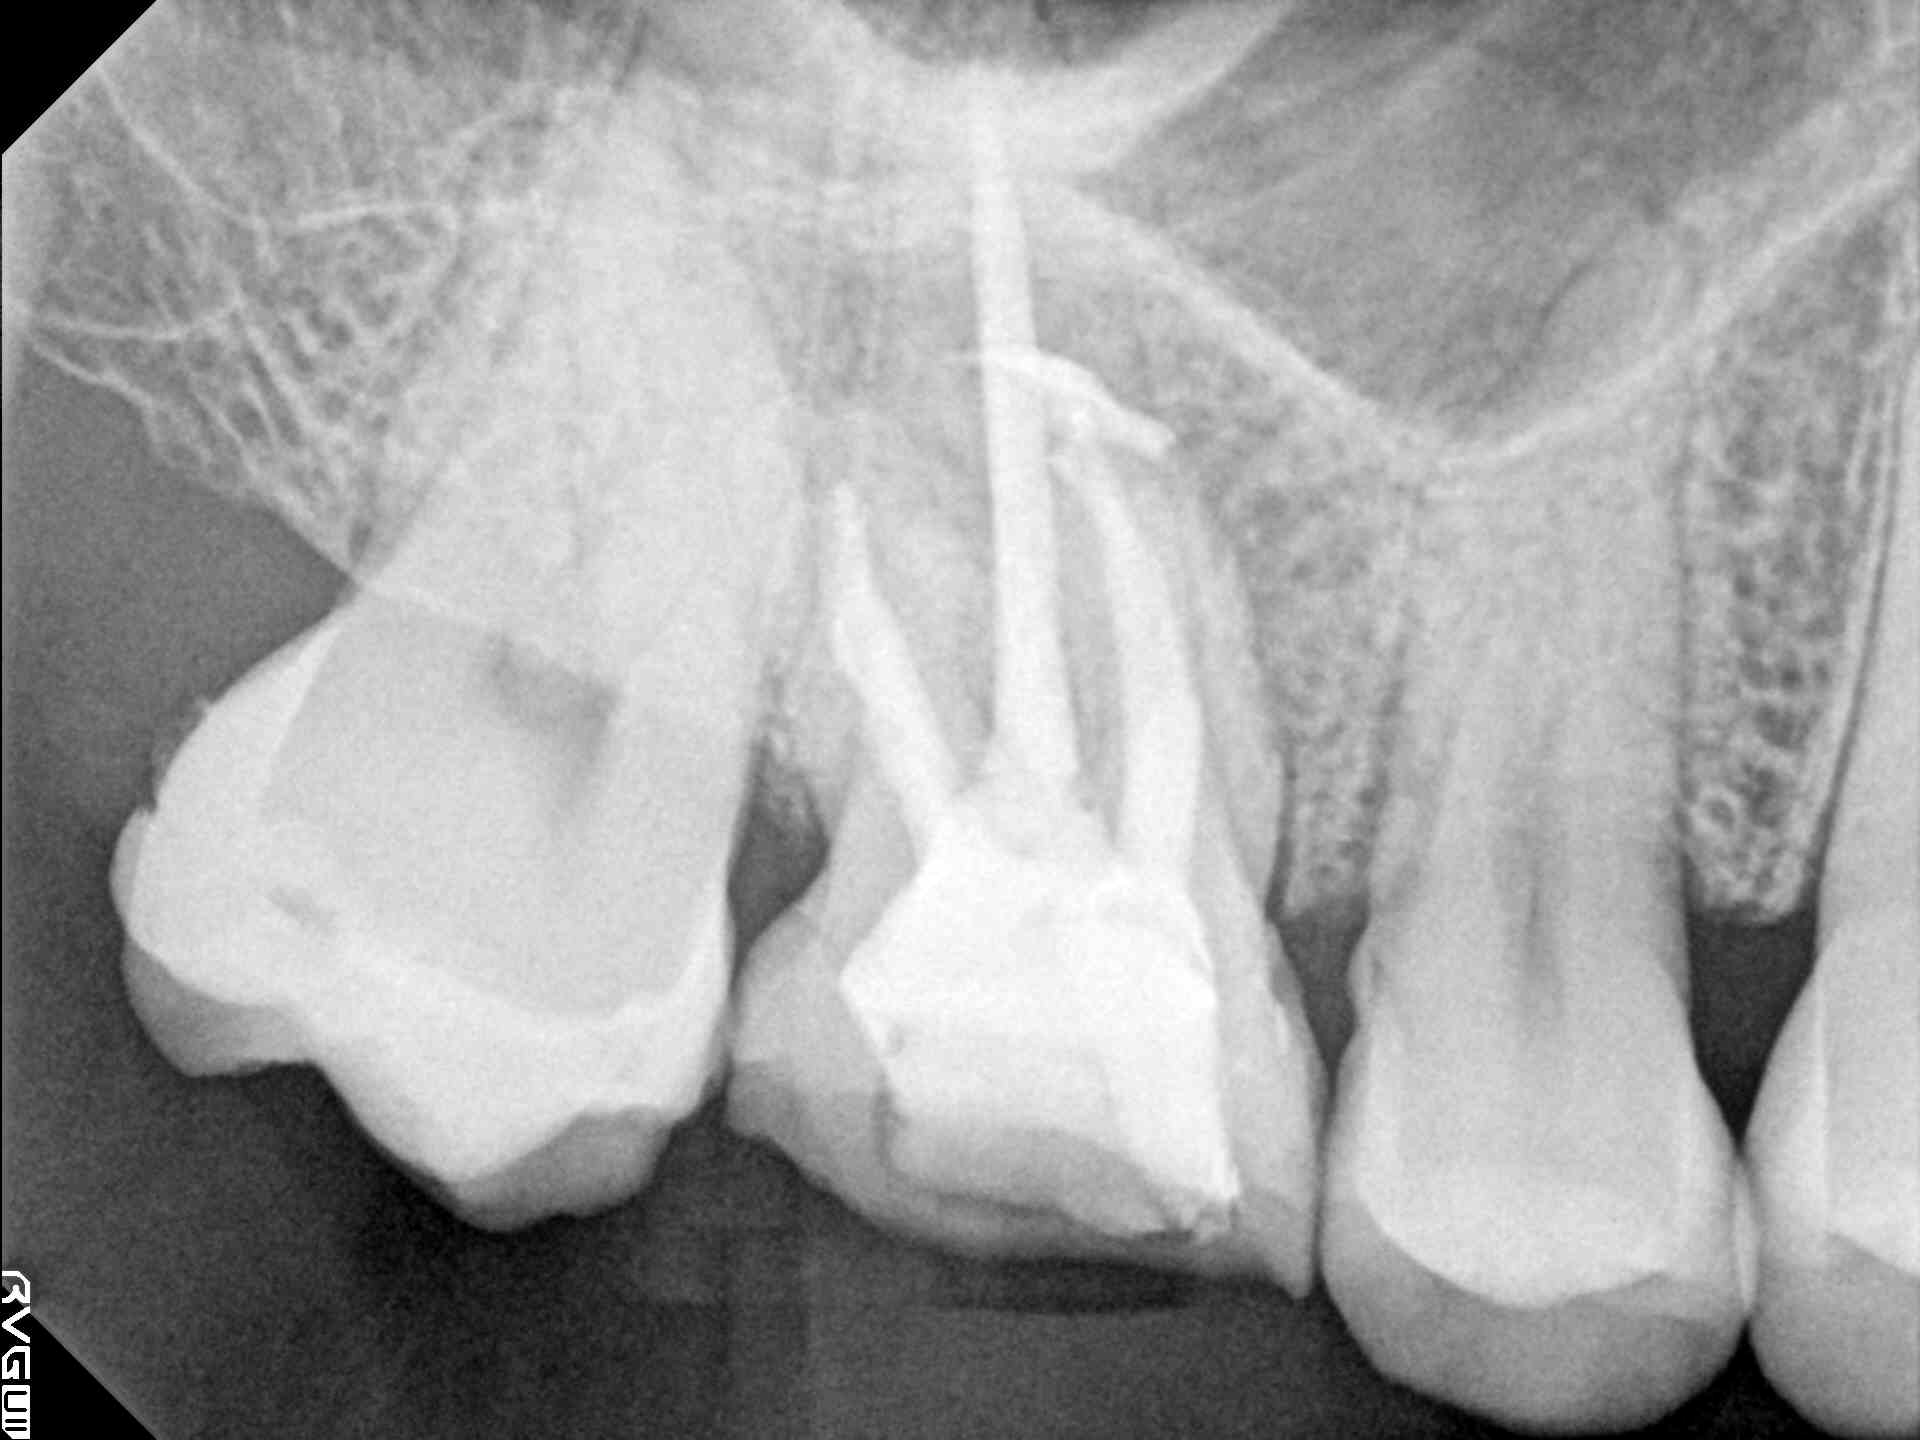

| 写真 根管1、2 |

マイクロで中を綺麗にした根管 写真 根管3、4 |